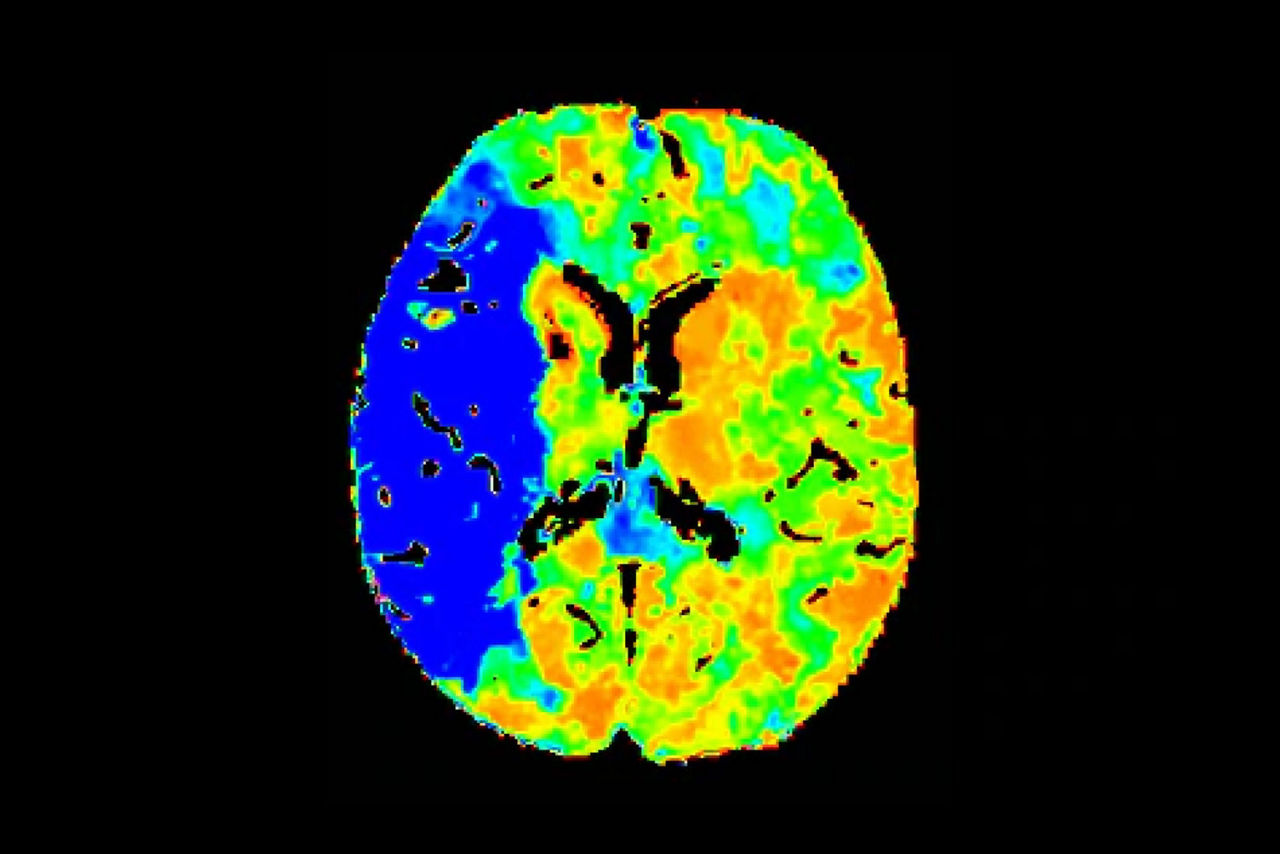

Post-scan

Neuro post-processing features

FastStroke delivers a fully automated processing platform for CT ischemic stroke studies.

On-console applications automatically process and send images to your stroke team via email.

Automated post-processing applications facilitate image review directly at the scanner or from one of up to four remote clients, which can all be accessed simultaneously.